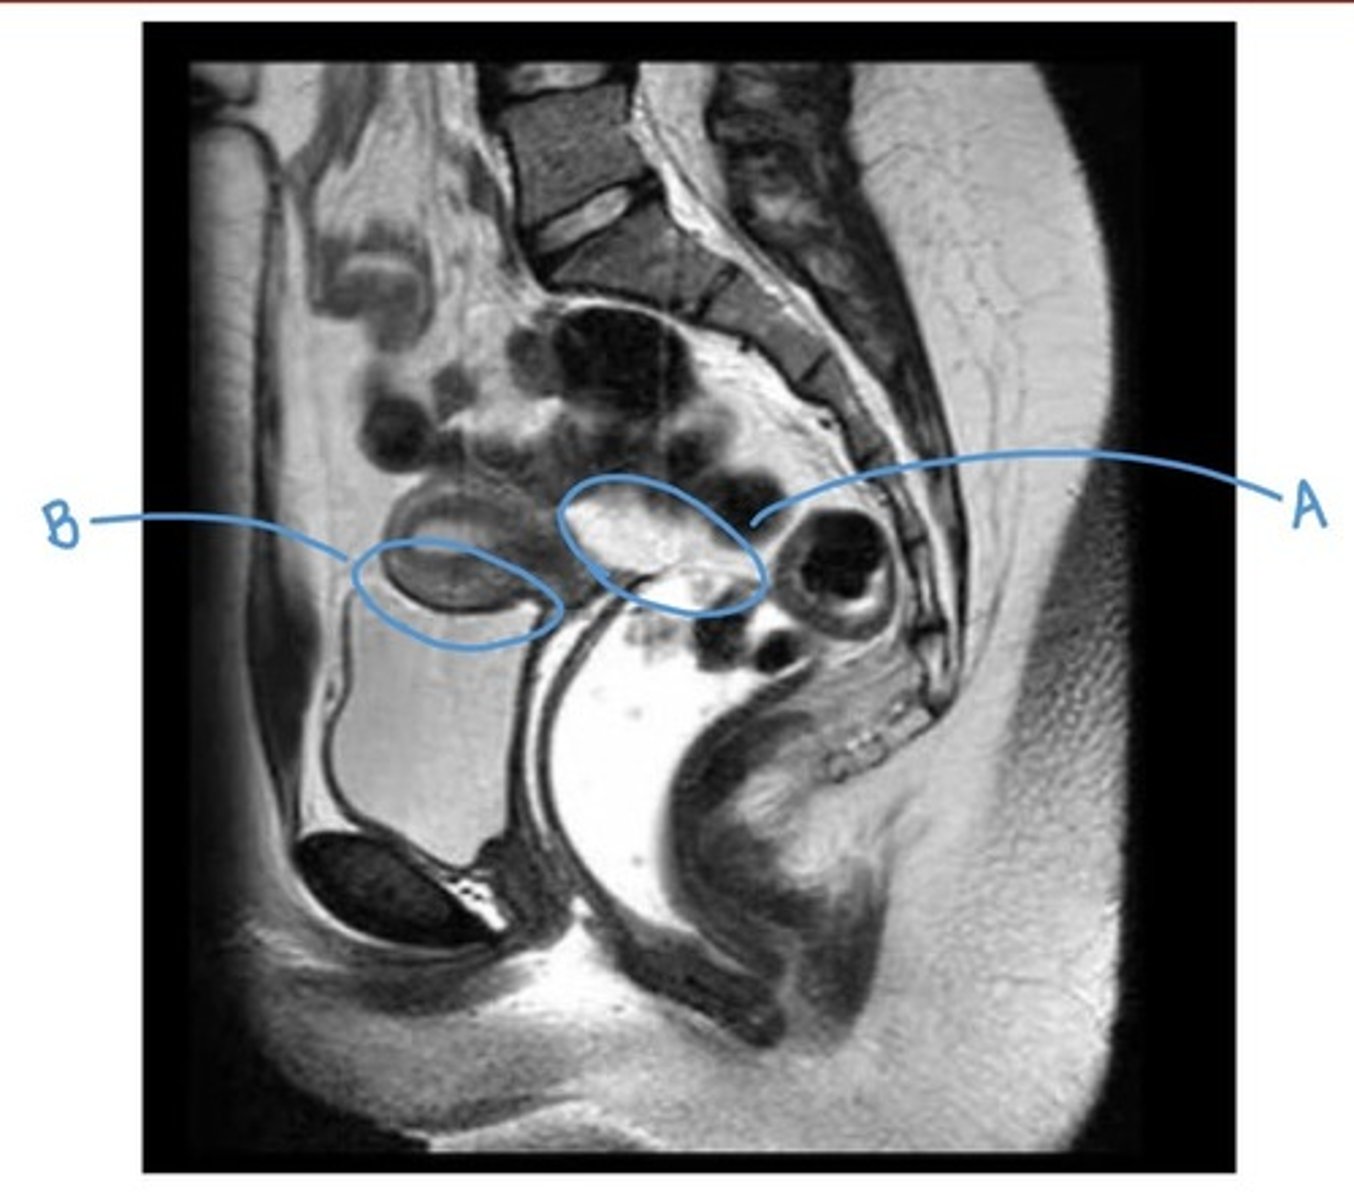

recto-uterine pouch

A

vesico-uterine pouch

B